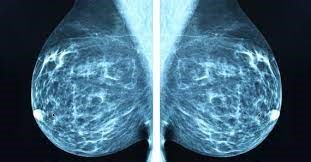

كشف سرطان الثدي باستخدام تقنيات Machine learning (م.د ميثم نبيل مقداد)

يُعتبر سرطان الثدي من أكثر أنواع السرطانات شيوعًا بين النساء حول العالم، مما يجعله موضوعًا هامًا للبحث والتطوير في تقنيات الكشف المبكر. تعتمد تقنيات Machine learning على خوارزميات معقدة لتحليل البيانات والتعرف على الأنماط، مما يسهم في تحسين دقة الكشف عن السرطان.<br />تقنيات Machine learning<br />تتضمن تقنيات Machine learning استخدام نماذج تعلم الآلة مثل الشبكات العصبية، والأشجار القرار، والدعم الآلي (SVM) لتحليل البيانات الطبية. تستخدم هذه النماذج في معالجة الصور الشعاعية للثدي، مثل صور Mammogram ، للكشف عن التغيرات غير الطبيعية.<br />عملية الكشف<br />تبدأ عملية الكشف بتجميع بيانات الصور الشعاعية، والتي تُستخدم كمدخلات لنماذج Machine learning. يتم تدريب النماذج على مجموعة كبيرة من البيانات المسجلة، مما يتيح لها تعلم الأنماط المرتبطة بسرطان الثدي. تشمل العمليات المختلفة تحليل الأنسجة، والتغيرات في الشكل والحجم، وتقدير كثافة الأنسجة.<br />التحديات<br />على الرغم من التطورات الكبيرة في هذا المجال، فإن هناك تحديات عدة تواجه تقنيات Machine learning في كشف سرطان الثدي. تشمل هذه التحديات الحاجة إلى بيانات تدريب عالية الجودة، وضمان دقة النماذج في تصنيف الصور بشكل صحيح. بالإضافة إلى ذلك، يُعد تكامل هذه الأنظمة في الرعاية الصحية الحالية تحديًا يتطلب استثمارات وتدريبات متقدمة.<br />الفوائد<br />تُظهر الدراسات أن استخدام Machine learning يمكن أن يُحسن من دقة الكشف عن سرطان الثدي مقارنةً بالطرق التقليدية. حيث تساهم هذه التقنيات في تقليل معدلات الأخطاء في التشخيص، مما يتيح العلاج المبكر ويساهم في تحسين نتائج المرضى.<br />المستقبل<br />يتجه البحث في هذا المجال نحو تحسين نماذج Machine learning لتكون أكثر دقة وسرعة. كما يُتوقع أن تساهم التطورات في مجال الذكاء الاصطناعي في تعزيز قدرة النماذج على التكيف مع البيانات الجديدة وتحسين أدائها. تُعد تقنيات الماشين ليرنك أداة قوية في الكشف المبكر عن سرطان الثدي، مما يُسهم في تحسين نتائج العلاج وزيادة فرص الشفاء. من المهم مواصلة البحث والتطوير في هذا المجال لضمان استفادة أكبر عدد من المرضى.